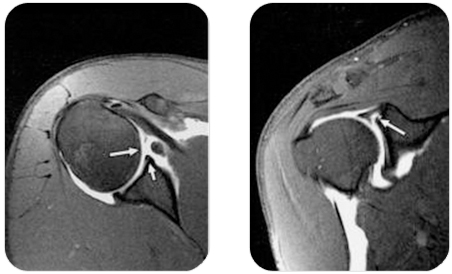

팔을 어깨 위로 반복적으로 들어올리는 경우나 어깨관절에 직접 가해지는 물리력에 의해 발생하는 경우, 40대 이후에서 회전근개 건병증과 연관되어 발생하는 경우 등 여러가지 상황이 있을 수 있습니다.

고령층에서 상부관절와순 후방부의 경도 분리는 정상적인 범주로 간주됩니다. 야구에서 던지는 동작이라든지, 머리를 감는 동작, 수영에서 팔을 뒤로 드는 동작 등을 할때 통증이 발생합니다. 젊은 환자의 경우는 수술적 치료가 필요합니다.

상부관절와순 파열은 형태에 따라 치료방법에 약간씩 차이가 있으나 대개 헤어진 부위는 관절내시경으로 매끈하게 다듬고 관절와에서 떨어져 나와 불안정한 부위는 관절와에 붙이는 수술을 하게 됩니다.